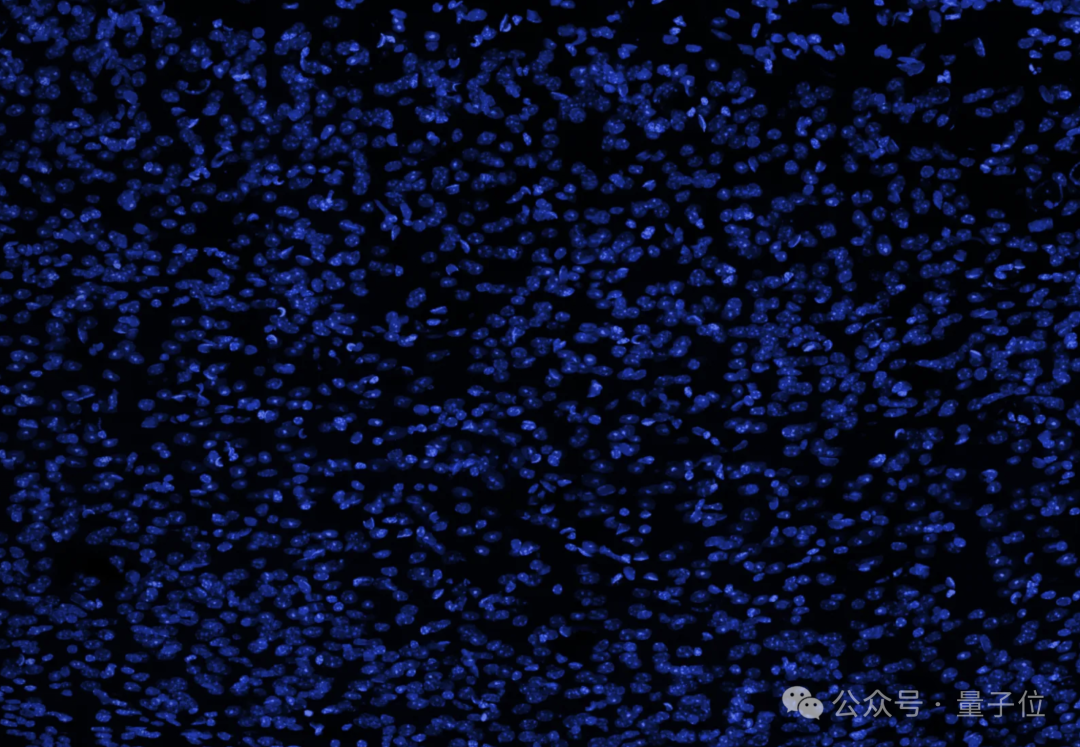

研究团队展示了一张大脑的横截面图像(蓝色表示细胞核),并表示人脑中看似空旷的空间实际上充满了轴突、树突和支持细胞,形成了密集的突触网络。